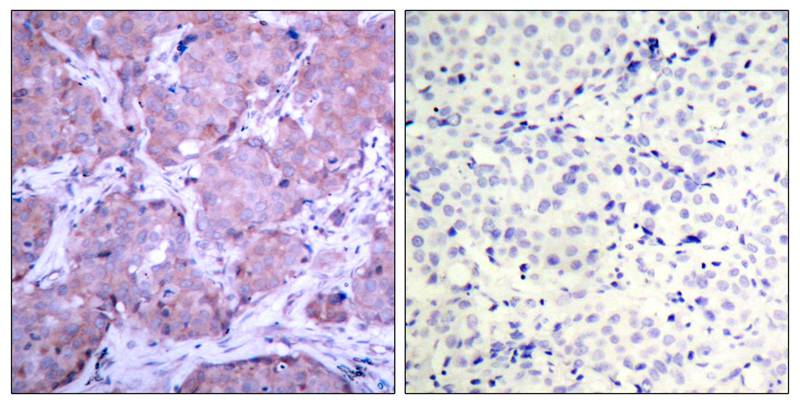

分类: 科研抗体货号: P20336别名: PTEN; MMAC1; TEP1; Phosphatidylinositol 3; 4; 5-trisphosphate 3-phosphatase and dual-specificity protein phosphatase PTEN; Mutated in multiple advanced cancers 1; Phosphatase and tensin homolog应用: IHC,IF反应种属: Human,Mouse,Rat